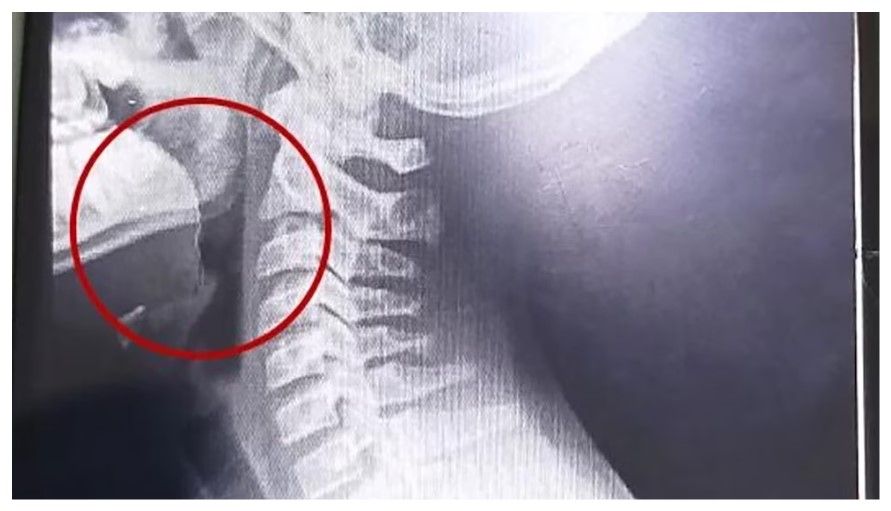

El hospital Materno Infantil de Mar del Plata halló mediante estudios por imágenes un alambre fino incrustado en la garganta del paciente (0223)

A continuación, se desarrollaron distintos estudios para descartar la presencia de infecciones o bacterias, cuyos resultados resultaron negativos. La clave para entender el cuadro apareció tras la realización de estudios por imágenes: las placas evidenciaron la presencia de un objeto extraño alojado en la vía aérea superior.

El parte médico consignó que el paciente ingresó “clínica y hemodinámicamente estable, afebril, vigil, reactivo, normohidratado y normoperfundido”, según el medio local. Luego de una interconsulta con el servicio de otorrinolaringología, se resolvió su ingreso urgente a quirófano. Allí, el equipo médico halló un alambre fino incrustado en la garganta del adolescente, situación que no había sido advertida previamente.